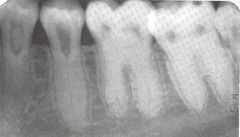

focal sclerosing osteomyelitis

-asymptomatic, bone adjacent to any tooth radiopaque area below roots -Mandibular 1st molar most common